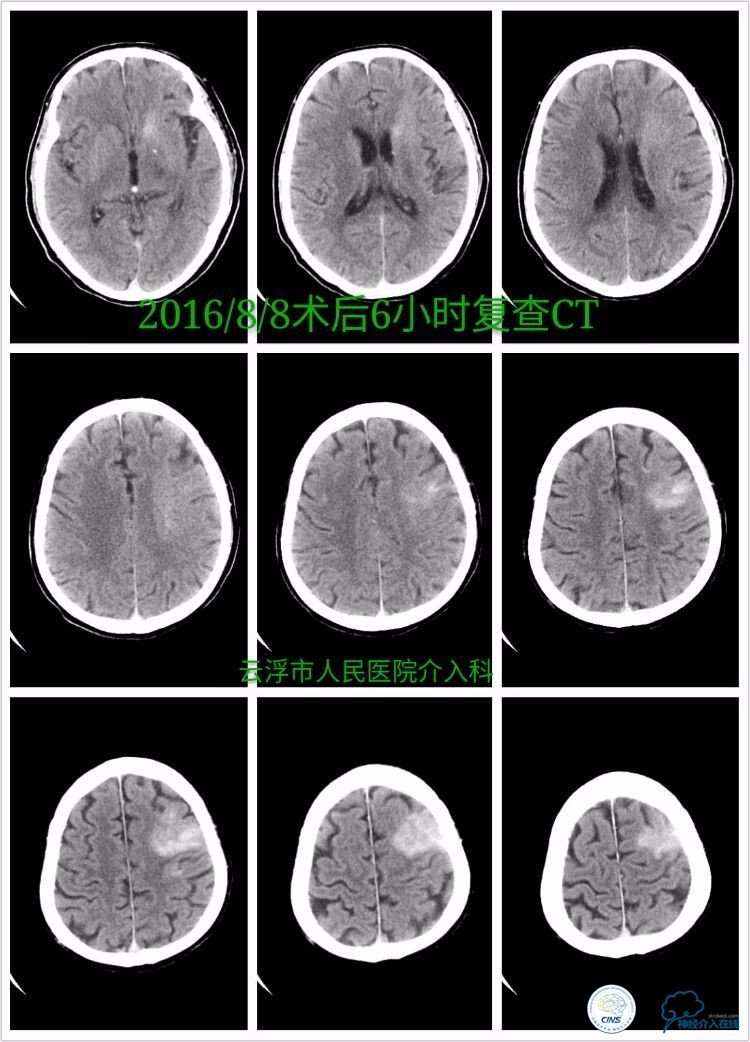

》术后第6小时复查颅脑CT:

》术后第四天颅脑CT:

术后第1周内观察患者认知、言语功能改善明显,右侧肢体肌力0级。

术后第3周观察患者部分混合性失语,右侧肢体上肢1级,下肢2级。